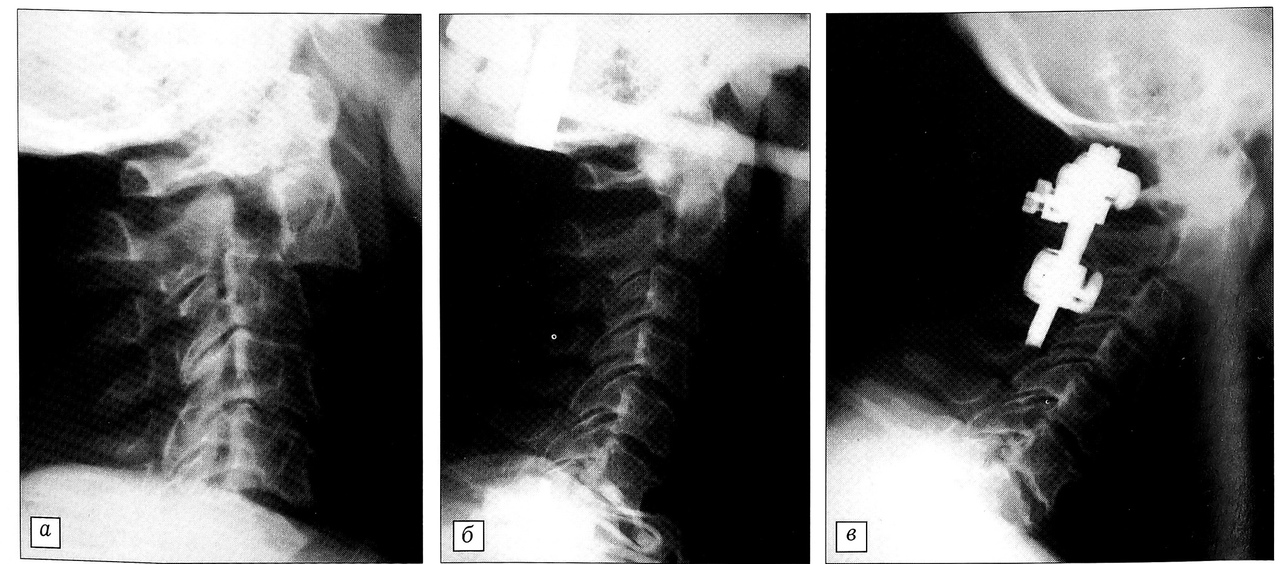

В 12 случаях гало-аппарат был применен при переломе дуг С2 позвонка. Линия перелома у 8 больных проходила через корень дуг С2 позвонка, а у 4 атипично — косо через дугу и тело С2. У 9 пациентов перелом сопровождался спондилолистезом тела позвонка кпереди (рис. 1).

Рис. 1. Больной 62 лет: a — травматический спондилолистез С2 позвонка; б — репозиция в гало-аппарате; в — стабилизация С1-3 сегментов системой «CCD Cervical»